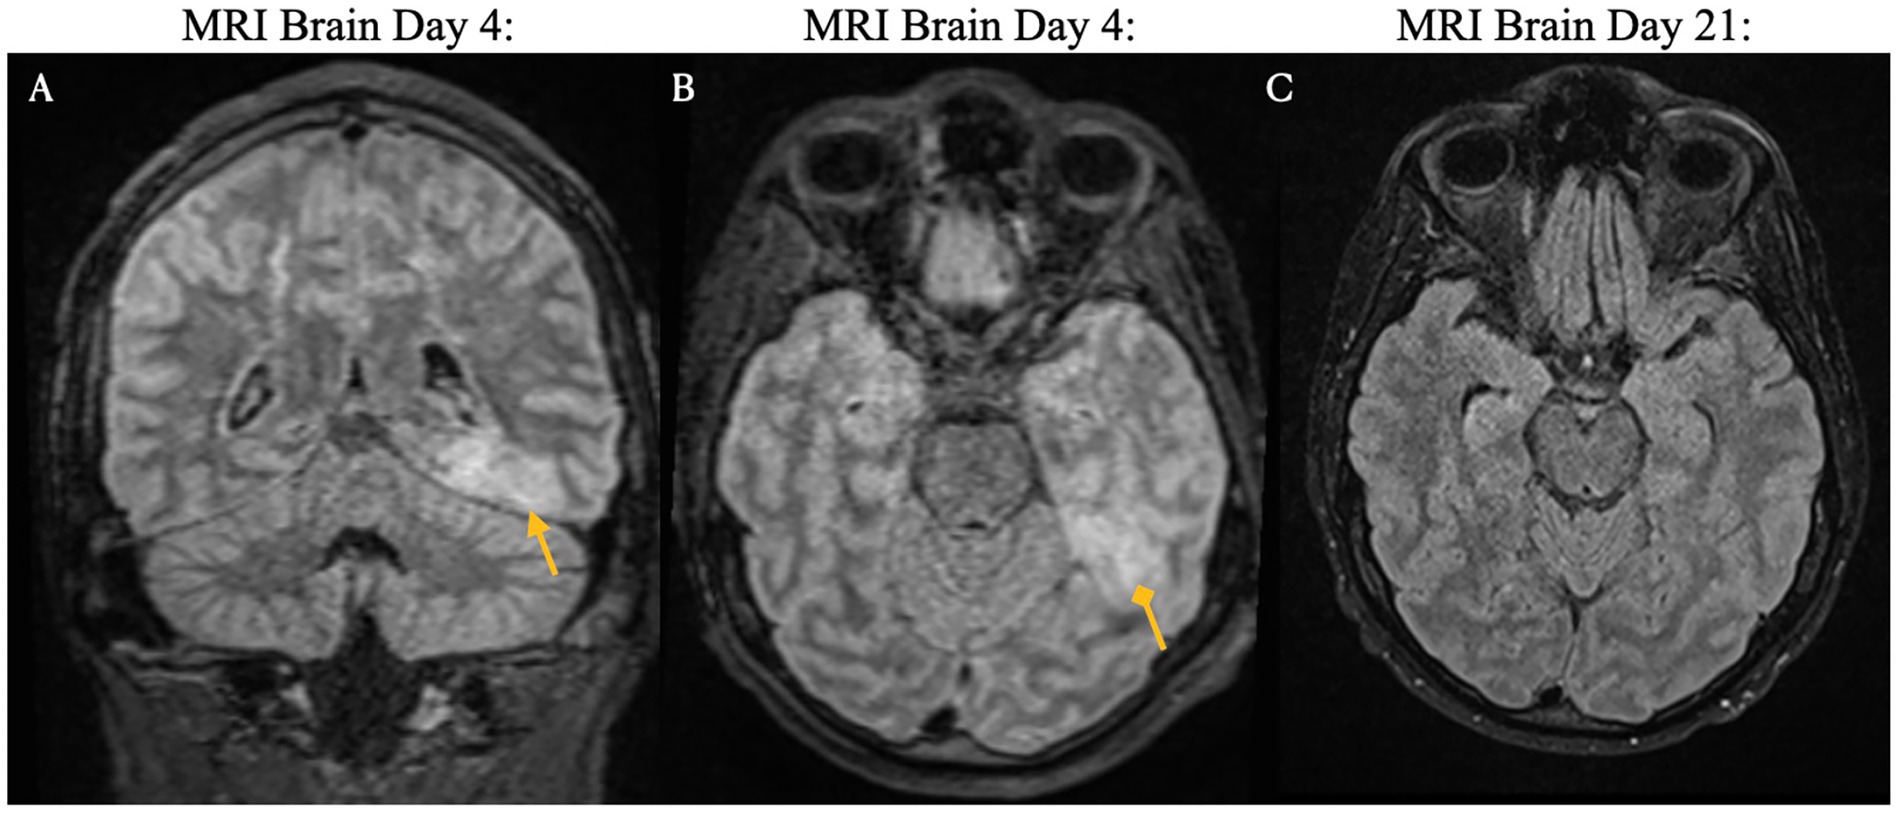

The clinical timeline for this patient is illustrated in Figure 2. One day after CAR T-cell therapy, the patient developed persistent fevers consistent with grade 1 CRS, and was treated with tocilizumab, resulting in resolution of the fever. However, 3 days later, he experienced recurrent grade 1 CRS with fever and grade 1 immune effector cell-associated neurotoxicity syndrome. The patient’s condition rapidly deteriorated, progressing to grade 3 ICANS (aphasia) and subsequently to grade 4 ICANS, characterized by seizure activity. On day five, he was intubated for airway protection and transferred to the intensive care unit (ICU). MRI of the brain revealed diffuse leptomeningeal enhancement, widespread T2 and FLAIR hyperintensities throughout the cortex and pons (Figure 3), and focal FLAIR hyperintensity in the left mesial temporal lobe (Figure 4), potentially related to recent seizure activity. These neuroimaging findings were consistent with ICANS-associated changes. The patient was started on dexamethasone and anakinra for the management of ICANS-related neurotoxicity, and by the following day, there was a marked reduction in leptomeningeal enhancement.

Figure 3

MRI images comparing brain scans on Day 4 and Day 21. Images A, C, and E show Day 4 with arrows indicating abnormalities. Images B, D, and F show Day 21 with reduced abnormalities, suggesting improvement.

Figure 3. Brain magnetic resonance imaging on days 4 and 21 following CAR T-cell infusion. ICANS-associated brain MRI findings. T2 and FLAIR sequences reveal hyperintensity throughout the cortex and pons, accompanied by diffuse leptomeningeal enhancement. Images were acquired pre-treatment (Day 4 Panels A,C,E) and post-treatment (Day 21. Panels B,D,F) following steroid and Anakinra therapy.

Both the present case and the case described by Koch et al. developed immune effector cell associated neurotoxicity syndrome. In the Koch et al. case, the patient exhibited simultaneous onset of grade 2 ICANS (disorientation) and GBS-like symptoms on day five, with no ICANS related findings on brain MRI. In contrast, our patient developed grade 1 ICANS on day three, which progressed to grade 3 (aphasia) and grade 4 (seizures) by day four. Brain MRI in our presented case revealed imaging features typical of ICANS, including leptomeningeal enhancement and diffuse T2/FLAIR hyperintensities in the cortex and pons. These findings resolved with treatment using dexamethasone and anakinra. However, following extubation on day nine, the patient developed new-onset neurological deficits and spinal MRI findings consistent with Guillain-Barré syndrome following apparent resolution of ICANS.